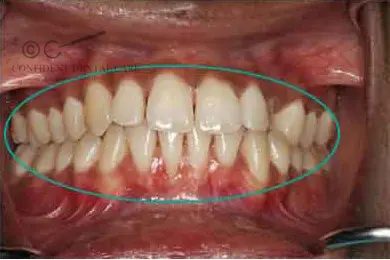

These cover treatments associated with gum diseases thus minimising:

- Bleeding gums

- Loose teeth

- Appearance of gaps in between teeth

- Painful gums

- Bad breath

Varied gum treatments such as root planning, flap surgeries, gingival depigmentation, general aesthetic surgery, etc. are also included under periodontics.